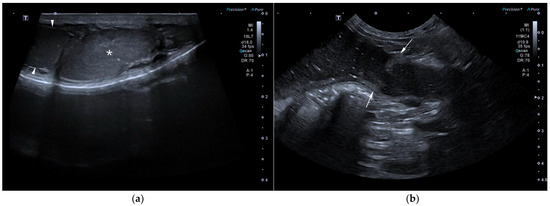

Computed Tomographic and Ultrasonographic Features in Three Dogs with Infected Uterus Masculinus and Concurrent Genital Neoplasia

Uterus masculinus is a rare disorder of sexual development in males, characterized by the presence of tubular female genitalia. Diagnostic imaging reports of infected uterus masculinus are limited. We describe the ultrasonographic and computed tomographic findings in three dogs, all presenting with abdominal distension, pain, and systemic infection. Imaging consistently revealed a fluid-filled, bicornuate structure arising from the prostate. In two dogs, the horns extended through the inguinal rings to the scrotal testes; in the third, with a prior left orchiectomy, both horns were intra-abdominal, the right ending in a peritoneal mass. Surgery and histopathology confirmed infected uterus masculinus, with Escherichia coli isolated from urine in all dogs and from the structure in two. Two dogs had Leydig cell tumors, one with concurrent uterine neoplasia; the third had an ovarian or ovotesticular granulosa cell tumor. Although rare, infected uterus masculinus is potentially life-threatening and should be considered in male dogs with abdominal pain, distension, or systemic infection. This is the first case series describing combined ultrasonographic and tomographic features of infected uterus masculinus, including novel findings such as cervix-like mural narrowing and fluid–fluid levels. It is also the first imaging description of an ovarian or ovotesticular tumor in a dog with uterus masculinus. Full article

Figure 1